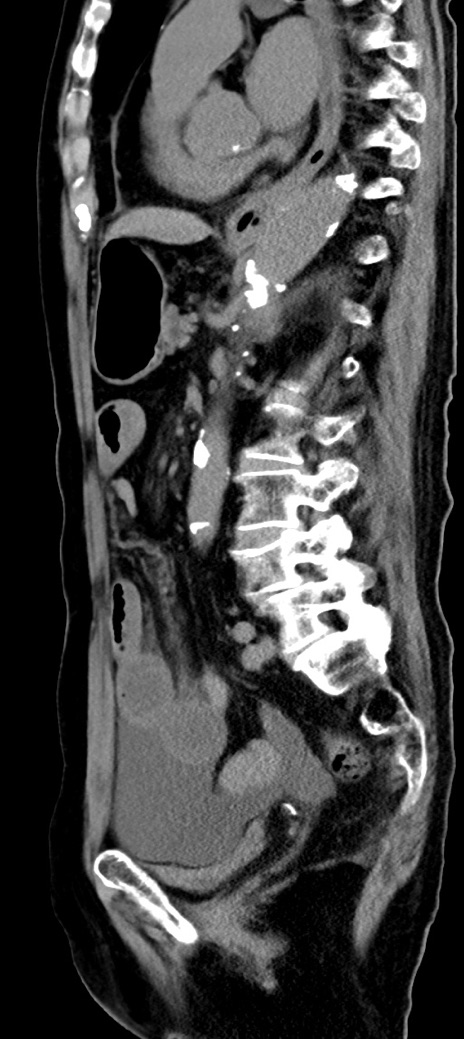

症例40(矢状断像)他院1日前

【症例】90歳代女性

【主訴】腹痛・嘔吐

【現病歴】 食欲低下、嘔吐があり昨日他院受診。肺炎と診断され入院となる。入院後より腹部全体に圧痛あり。胃管留置され経過みていたが、症状持続するため、

当院転院となる。

【既往歴】胸椎圧迫骨折、胆石症

【身体所見】腹部:中央に激痛あり、圧痛あり、反跳痛不明

【データ】WBC 17100、CRP 18.82